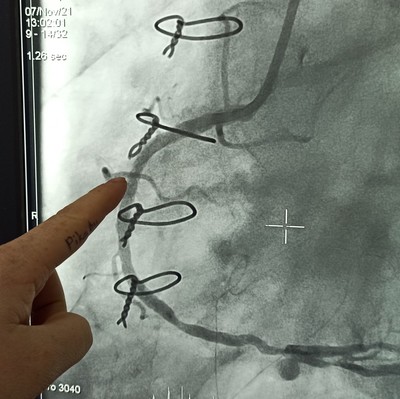

Мой палец, тычащий в только что установленный стент правой коронарной артерии.